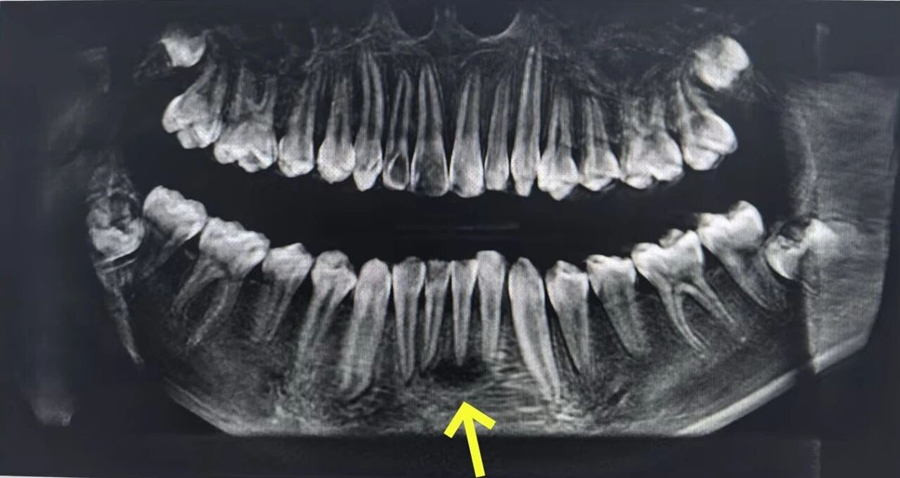

CBCT(口腔锥形束计算机断层扫描检查)提示根尖周大面积低密度影,结合牙髓电活力测试,最终诊断为31、32急性根尖周炎、牙周-牙髓联合病变!